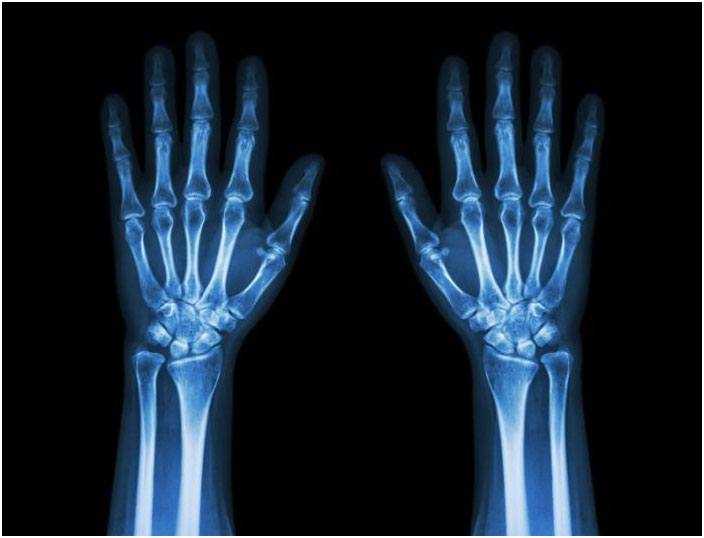

Doctors will often order an X-ray. In some cases, an MRI or CT scan may also be ordered.